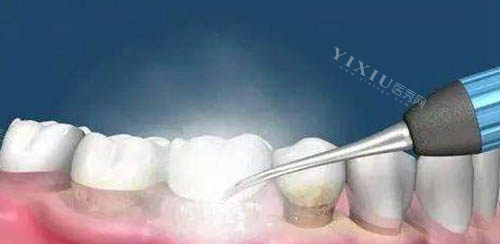

中浩口腔提供超声波洗牙、喷砂洁牙及牙周深度洁治服务,满足不同清洁需求。

喷砂洁牙:128元起/次。结合高压水流与特制喷砂粉,深层清洁烟渍、茶渍,适合牙齿表面色素沉着者。

独立消毒供应室确保器械“一人一用一消毒”,杜绝交叉感染。

洗牙后提供免费抛光服务,减少菌斑附着,延长清洁结果。